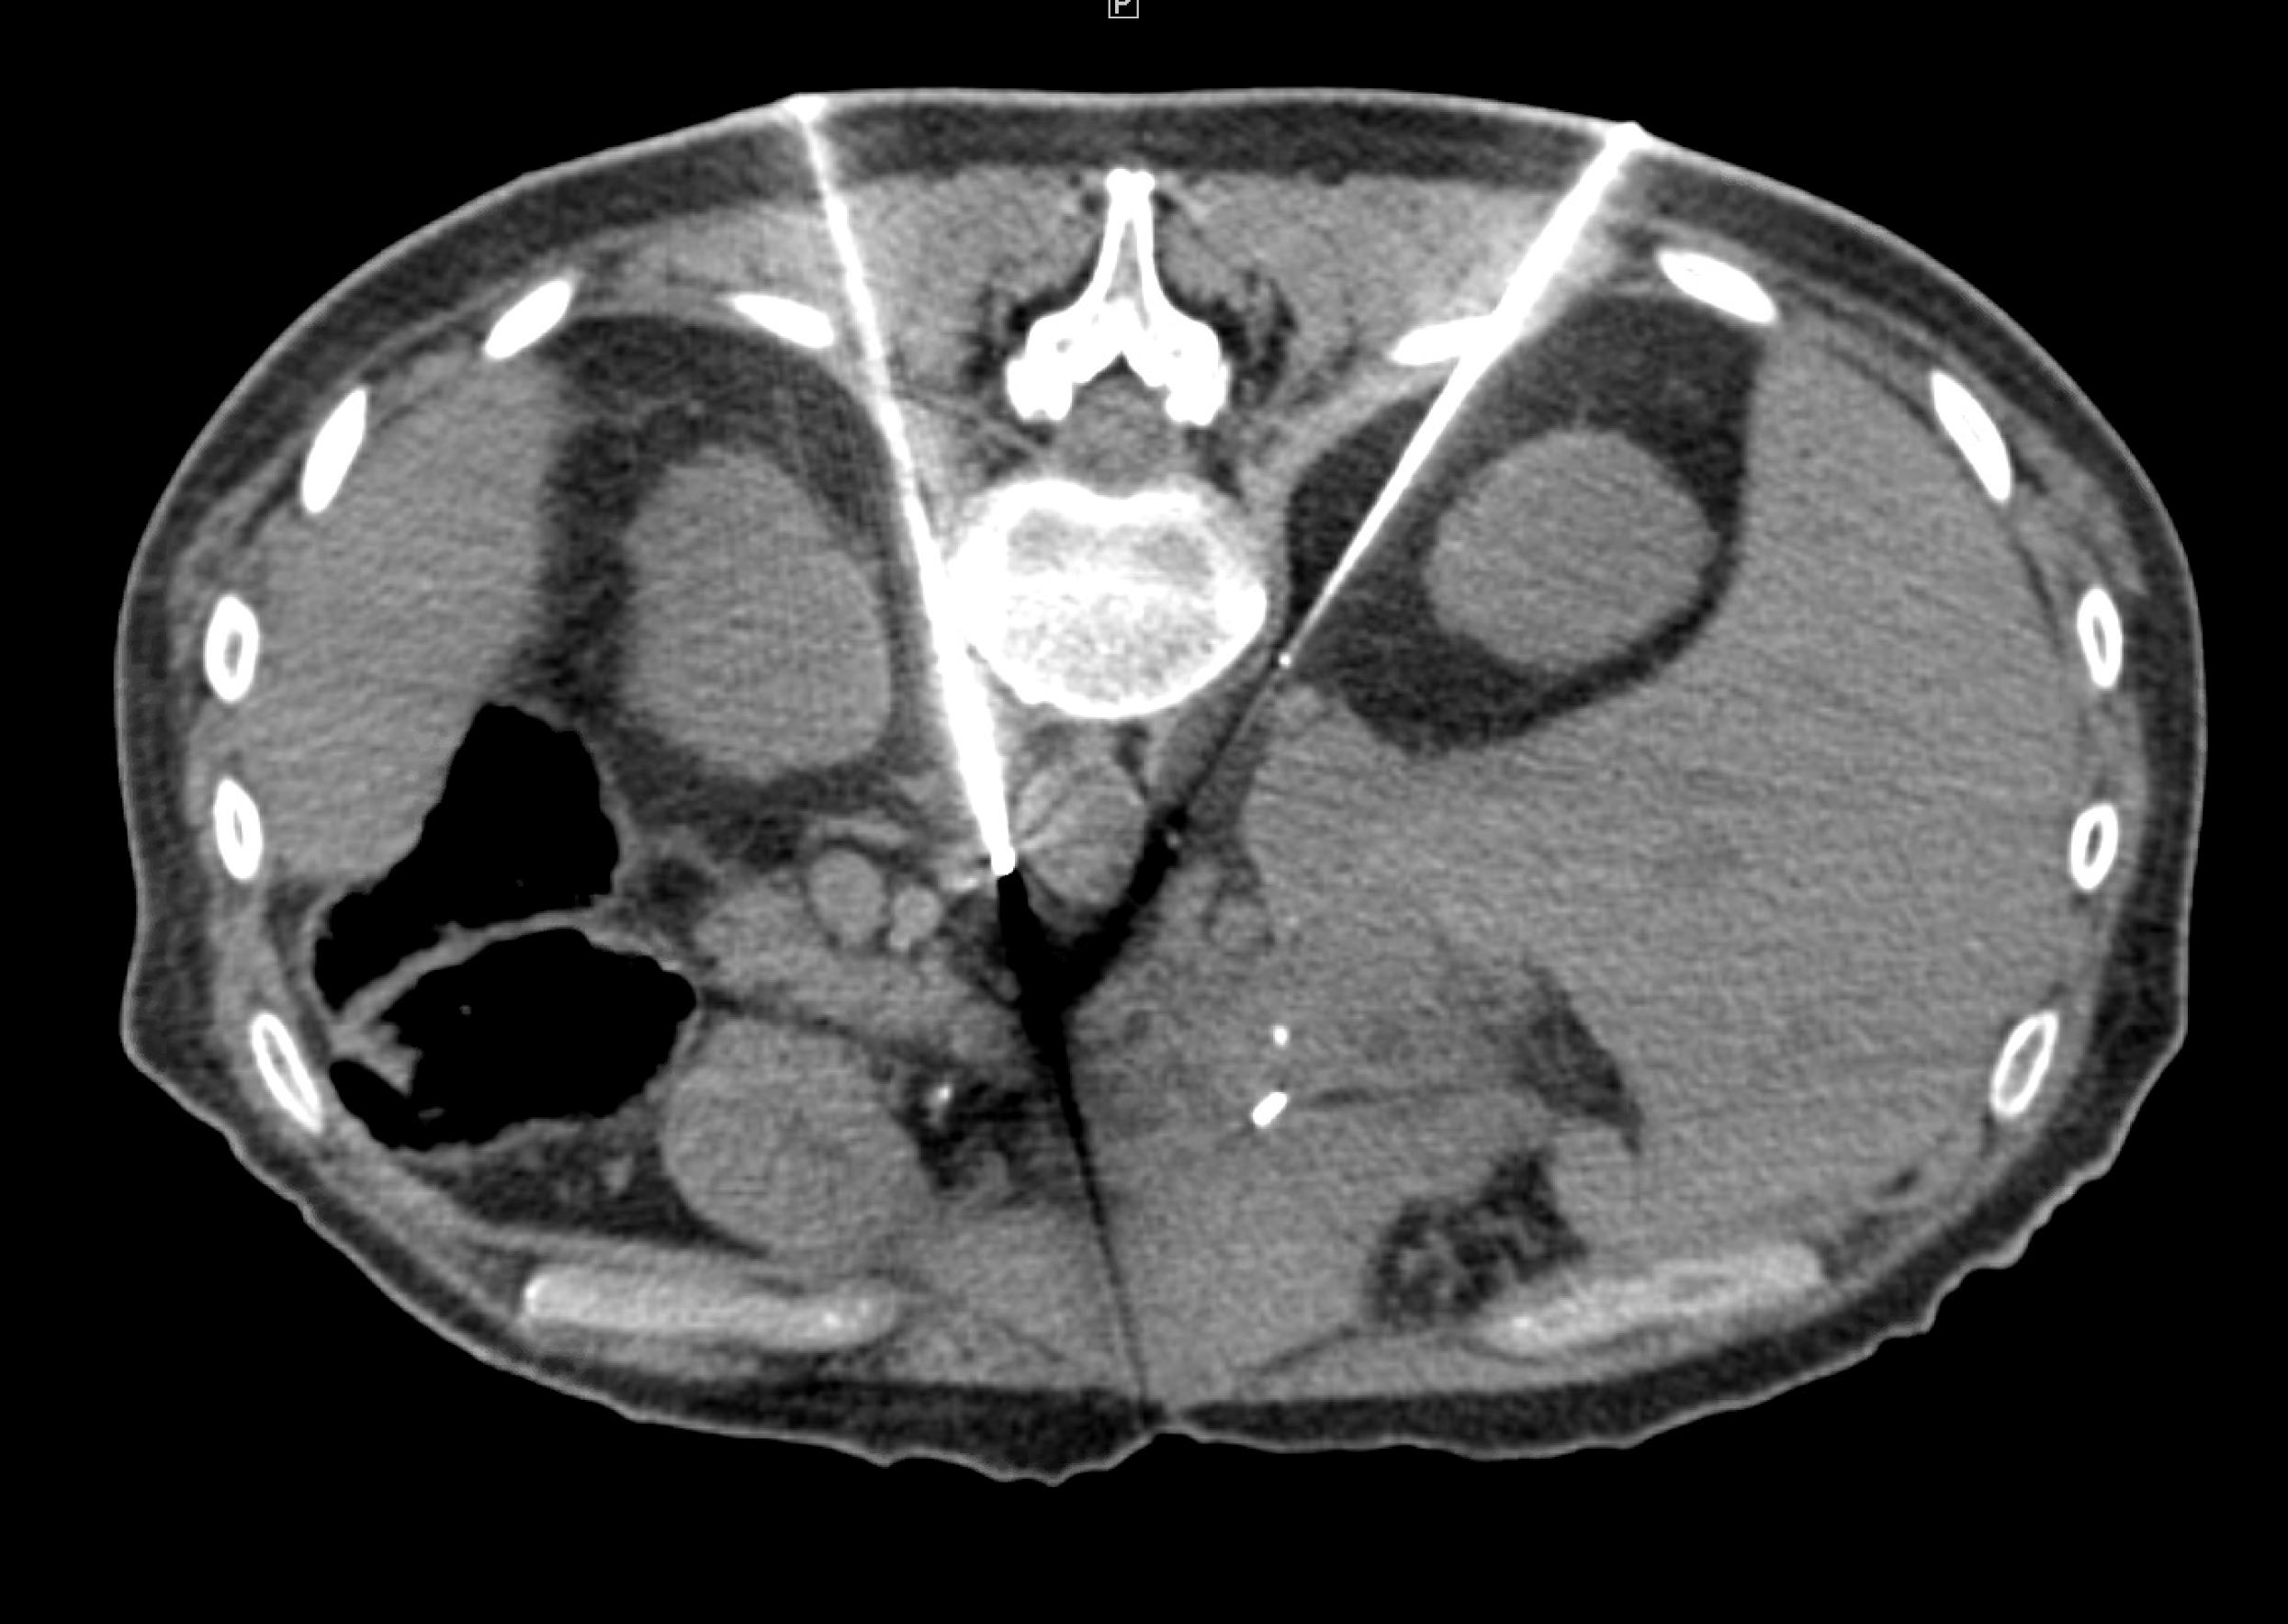

MRI image from Chary cryoneurolysis case MRI image from Chary cryoneurolysis case

Celiac Plexus Cryoneurolysis case study

A 66-year-old man presented with intractable upper abdominal pain refractory to medical management with opiates. MRI axial images through the celiac plexus at the celiac plexus at the level of the celiac axis and SMA origins demonstrate bulky retroperitoneal adenopathy and soft tissue tumor infiltrate. Two IceRod™ 1.5 CX needles were placed within and along the bilateral celiac plexus via CT-guidance. The CT Axial image (right) in prone position shows right-sided iceball formation along the celiac plexus demonstrating excellent coverage. The patient reported pain at 2/10 after a 3-day follow-up pain assessment; the pain score before the procedure was a 10/10.

Aron Chary, MD I MidSouth Imaging - Vascular Interventional Physicians I Memphis, TN